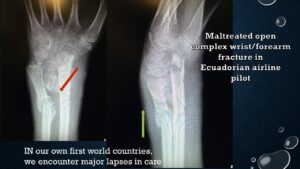

Diapositivas de presentación

Equidad en salud a través del conocimiento médico